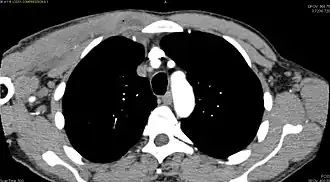

CT exam showing a multiloculated fluid collection in the left gluteus minimus muscle found to be a staph aureus pyomyositis in a 12-year-old healthy boy.